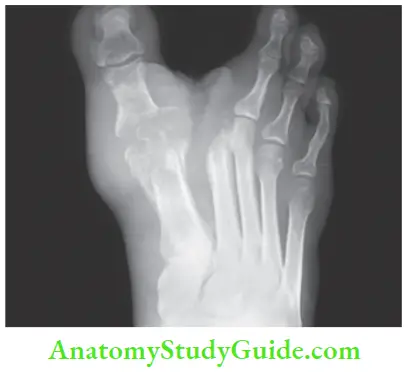

4. X-ray of the foot to be done to rule out osteomyelitis, which may be the cause of the chronicity of the ulcer. It takes weeks for visible changes of osteomyelitis on the radiograph. Today in all such doubtful cases, an MRI of the foot or leg is done.

- X-ray of the part: It is done to look for osteomyelitis— common in diabetic ulcers.